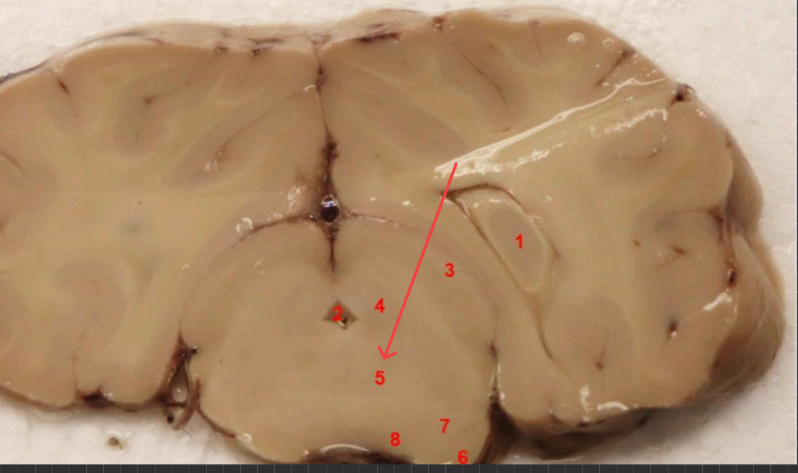

what is this

posterior commissure

splenium of corpus callosum

superior colliculs

cerebral aqueduct

periaqueductal gray

superior colliculus

red nucleus

what is this, function

ventral tegmental area , brain's reward system, motivation, and emotion regulation

substaina nigra, regulates voluntary movement, motor planning, reward-seeking, and addiction

cerebral punducle

what is this, function?

dorsal raphe nucleus , serotonin, (mood, sleep, emotion)

what is this , function

locus coerules , regulating arousal, wakefulness, attention, and stress responses

dorsal raphe nucleus

superior cerebellar punudcle, inferior cerebellar punducle

what is this , function?

Reticular formation arousal, consuoiunsess, sleepwake ( keeps u awake!!!)